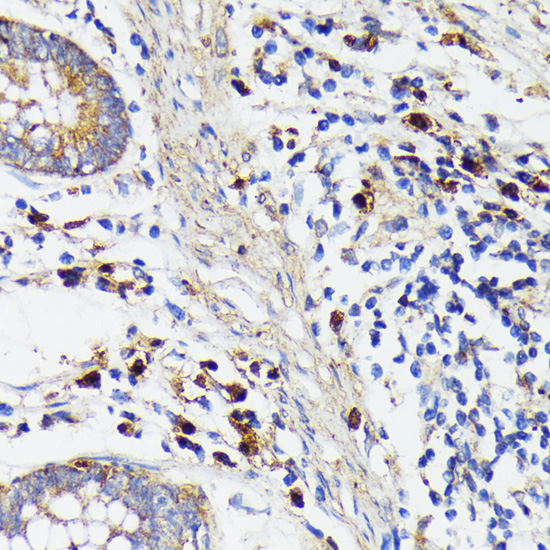

IHC 1/50-1/100 Human,Mouse,Rat